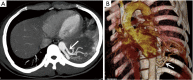

Results: Twenty-eight patients, 15 male and 13 female, with a median age of 42.5 underwent operative intervention for PS. Twenty-one patients showed preoperative symptoms including cough, expectoration, hemoptysis, chest and/or back pain, and fever. General chest computed tomography (CT) scanning; percutaneous needle biopsy, bronchoscopy, enhanced CT scanning, and CT angiography (CTA) were used as diagnostic methods. Twenty-one patients were diagnosed preoperatively by enhanced CT scanning and CTA; seven patients were confirmed by surgery. Twenty-one patients underwent surgery (15 cases via thoracotomy and 6 cases via video-assisted thoracic surgery), seven patients underwent interventional therapy (three cases via endovascular embolization and four cases via thoracic aortic endovascular stent-graft exclusion). Three patients had a complication in surgery group (intraoperative hemorrhage in two patients and postoperative hydropneumothorax in one patient) and two patients had post-embolization syndrome in interventional group (fever and pain at embolism site). During the follow-up period ranging from 6 to 84 months, no recurrences or further complications were observed in two groups.

Conclusions: Enhanced CT or CTA may be a potential approach for the diagnosis of PS. Surgical resection for PS is the major treatment approach. Endovascular embolization of PS could be considered when pulmonary lesion is small-sized. Endovascular exclusion could be used to treat combined arterial aneurysm and dissection of PS.